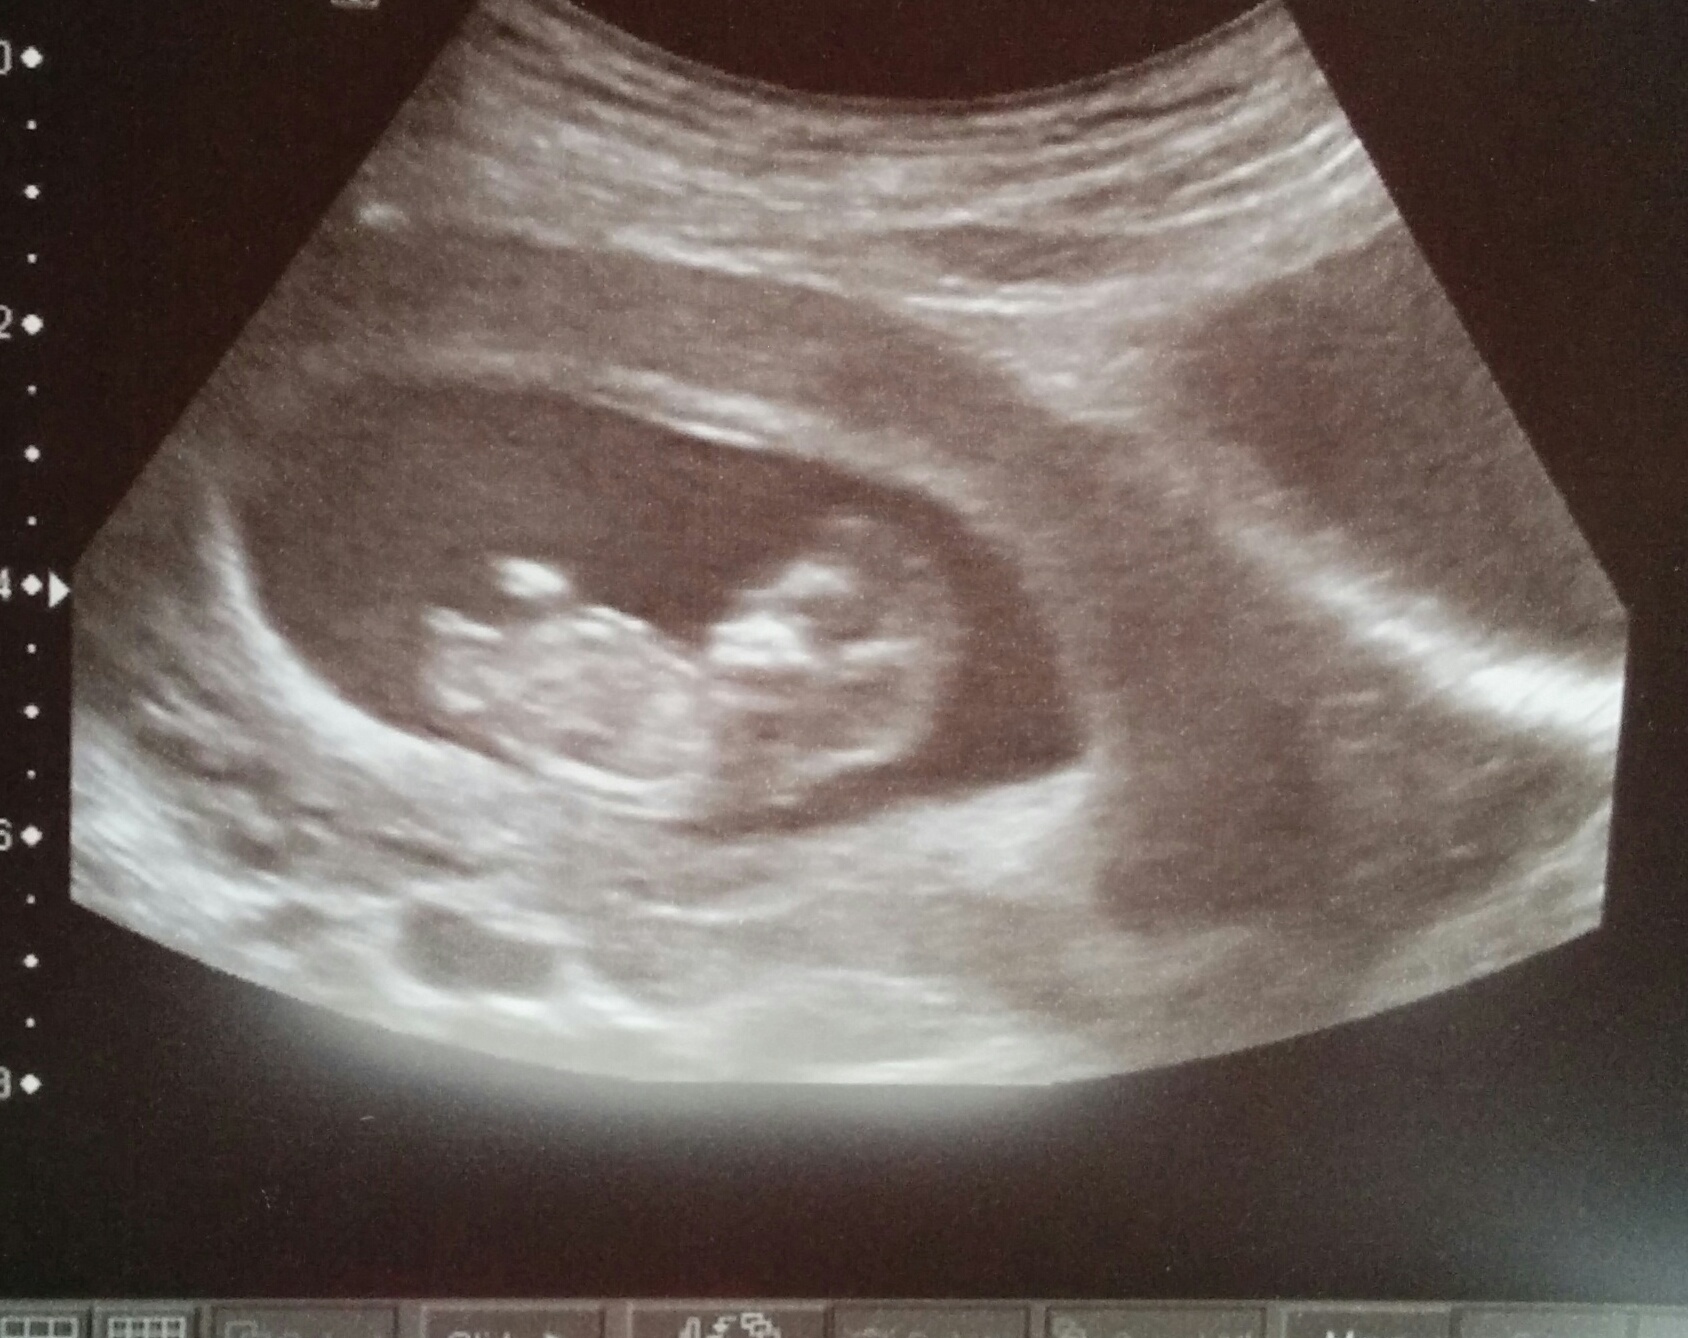

My MCMA twins a couple of weeks ago at 13 weeks gestation :-)